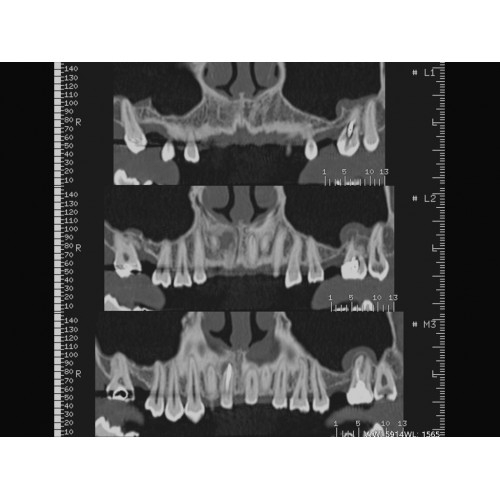

Травматология и ортопедия

• Диагностика сложных переломов и повреждений суставов.

• 3D-реконструкция костных структур для планирования операций.